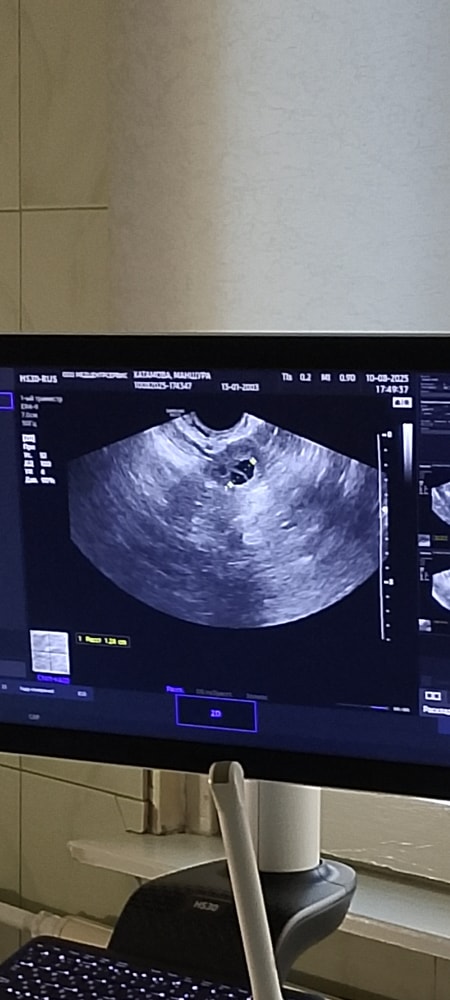

Здравствуйте девочки в прошлом раз была стимуляция овуляции с уколом хчг 10000 ме и фоликула превращался на киста жёлтого тела после укола 35 дц месячные пришли и потом на 6 дц, вчера была УЗИ а там вот такой картина это доминантный фолликула или киста жёлтого тела узистка нечего не говорила а моя гинеколог была на операции пожалуйста скажите кто сталкивался с такой проблемой (